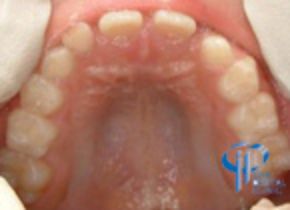

治療前

小児期の歯性の下顎前突ケースです。

上顎の中切歯2本が反対咬合です。また、正中が右側へずれています。

下顎歯牙の正中が顔貌の正中と一致しています。